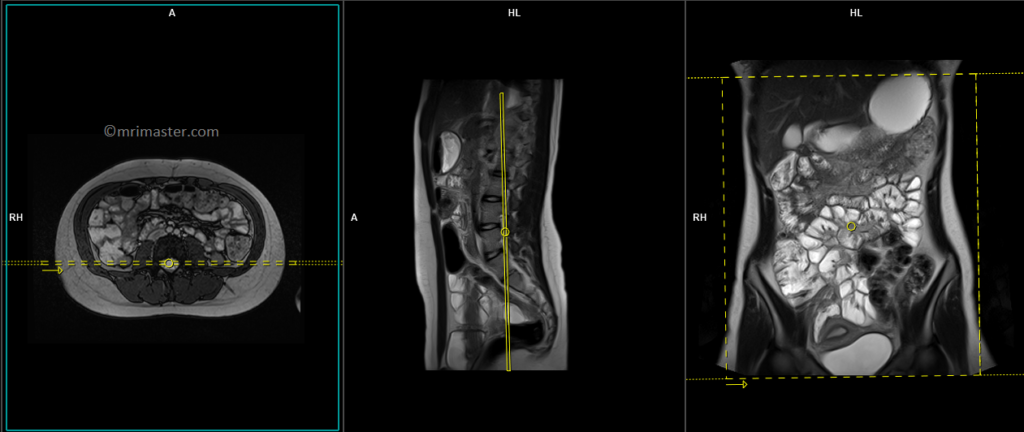

T1 VIBE DIXON \ T1 flash fat sat 3d 1-1.5 mm axial post contrast

Plan the axial slices on the coronal image, position the block horizontally across the abdomen as shown, and ensure that the positioning block is also checked in the other two planes. Establish an appropriate angle horizontally across the abdomen in the sagittal plane. The slices must be sufficient to cover the entire abdomen and pelvis from the stomach to the pubic symphysis. To prevent wrap-around artifacts, phase oversampling, and in the case of 3D blocks, slice oversampling must be used. Instruct the patient to hold their breath during image acquisition. (In our department, we instruct the patients to breathe in and out twice before giving the “breathe in and hold” instruction.)

The axial scan is performed as two separate blocks with a 10-25% slice overlap between them. The scan is performed this way to avoid any RF inhomogeneity-related artifacts by conducting the scans at the isocenter of the magnet. Use the composing function in the scanner to stitch the two blocks together.

Protocol Parameters T1 FLASH Axial

TR 3-4 | TE 1-2 | FLIP 12 | NEX 1 | SLICE 2 MM | MATRIX 320X320 | FOV 350-420 | PHASE A>P | OVERSAMPLE 30% | IPAT ON |